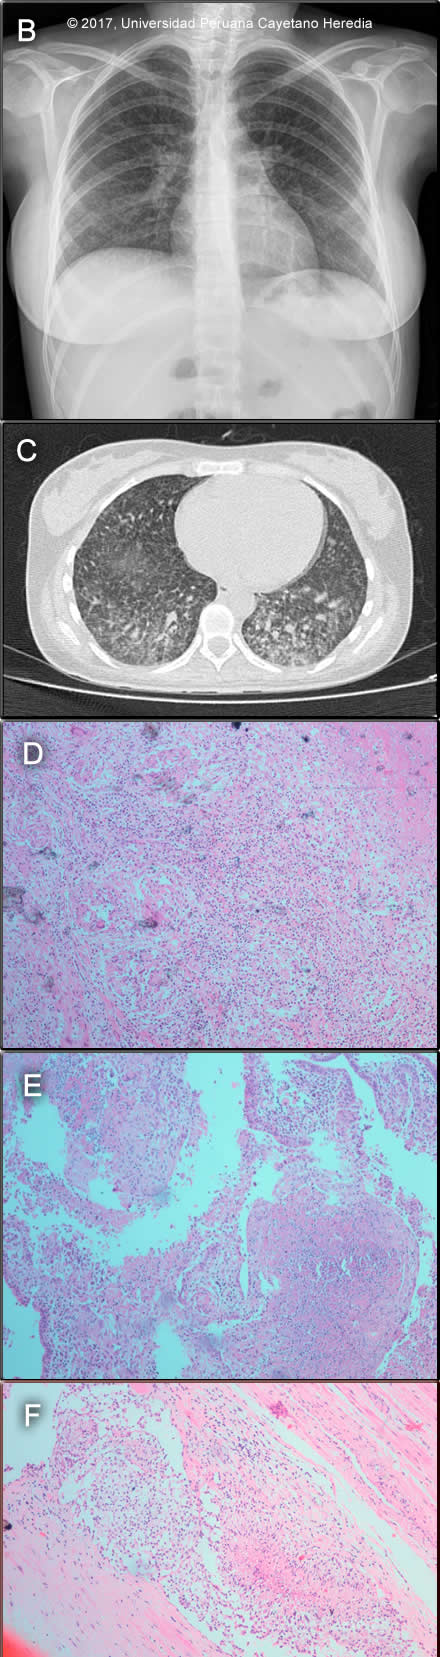

Epidemiology: Product of an uncomplicated pregnancy, dates unknown. UTI treated with vaginal medication 1 week prior to delivery. Two days of contractions with spontaneous rupture of membranes 12 hours before vaginal delivery. As reported by midwife, amniotic fluid was clear, placenta intact and completely expelled. Anthropometrics were all adequate for his estimated gestational age of 32 weeks. Immediately post-partum, the mother was found to be tachycardic, febrile and with vaginal bleeding and underwent puerperal curettage. She did not directly breast feed her infant during the hospitalization. Mother lives in San Juan de Lurigancho, Lima. Housewife, no risk factors for HIV infection, no history of recent travels. Physical Examination: HR 174, RR 58, T 36.8ºC, sO2 91% (FiO2 0.21). Moderately ill infant with respiratory distress. Skin: warm, dry, mild pallor. Capillary refill less than 2 seconds.Lungs: symmetrical chest, subcostal retractions. Normal breath sounds, no crackles..Heart: regular rate and rhythm, no murmurs. Abdomen: Distended, bowel sounds present. Liver 1cm below right costal border. Neurologic: somnolent, decreased reactivity to tactile stimuli. Axial and appendicular hypotony, weak suction. Laboratory: Hb 12.5 g/dL, Hct 35%. WBC 21.6 (2 bands, 54 neutrophils, 4 basophils, 1 eos,, 11 monos, 25 lymphs). Platelets 386 000. Blood type: O +, Mother: O+. Urea 16 mg/dL, creatinine 0.5 mg/dL. Na 137 mEq/L, K 5.04 mEq/L, Cl 102 mEq/L. AST 19 IU/L, ALT 15 IU/L, AP 365 IU/L. ABG: pH 7.347, pCO2 35.1, pO2 78.9, sO2 97.5%, HCO3 18.7. Urinalysis: WBC 0-3/hpf, RBC 0-2/hpf, few epithelial cells. Lumbar puncture: WBC 2/hpf (100% neutrophils), RBC 300/hpf, glucose 43, protein 171. Gram stain: negative. PPD: negative. Abdominal ultrasound: liver was normal, no hydronephrosis, no free fluid in the abdominal cavity. Chest X-Ray (see Image A).

![]() Discussion: On repeat testing, a gastric aspirate from the infant was positive for AFB (3+). Mother and baby were both HIV negative. Investigation of the mother, who remained febrile after the curettage, included chest X-ray and CT (Image B, C) showing a diffuse micronodular pattern. A pelvic CT (not shown) showed a large heterogeneous uterus which on examination after hysterectomy with bilateral salpingectomy, showed a chronic granulomatous process with giant multinucleated cells in the endometrium, myometrium (Image D) and Fallopian tubes (Image E). In addition, vascular emboli of tissue with granulomatous reaction in the parametrium (Image F) were seen though Ziehl-Neelsen stain was negative. The mother remained febrile after surgery. The diagnosis of miliary tuberculosis in the mother with genital involvement and the finding of AFB in the child led to the diagnosis of congenital tuberculosis and the need to start antituberculous therapy (RIPE) in both. Congenital tuberculosis is the perinatal transmission of M. tuberculosis. It is thought to be acquired in any of the following ways: transplacentally, where the primary complex is found in the liver; by aspiration of infected amniotic fluid during birth, with the lungs as the primary focus, or ingestion of infected amniotic fluid, where the primary infection site is in the gut. [N Engl J Med. 1994; 330:1051–4]. The differential diagnosis in a newborn presenting with this clinical syndrome should include neonatal sepsis, toxoplasmosis, rubella, CMV, HSV (TORCH) , other congenital infections consider within the TORCH complex as others (O) including Syphilis, Parvovirus B19, VZV; HIV. In preterm newborn with respiratory distress consider hyaline membrane syndrome (respiratory distress syndrome). The Cantwell criteria for congenital TB are: Although in our case, there was no evidence of a liver primary complex on ultrasound, the presence of genital tuberculosis in the mother supports also transplacental acquisition of MTB. The diagnosis of tuberculosis in an infant is based on a TST result, which is often negative, and a chest radiograph or other radiologic studies in a patient with a compatible clinical syndrome. Microbiological confirmation should be made whenever possible by examining specimens such as gastric aspirate, ascitic fluid, endotracheal aspirate, middle ear fluid, and CSF [Pediatrics 1980;66:9804]. |